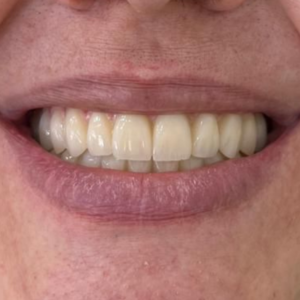

După 6 luni de la intervenție, procesul de osteointegrare s-a finalizat, iar implanturile s-au fixat complet în osul arcadei. Lucrarea temporară este acum înlocuită cu o lucrare fixă, de lungă durată, realizată pe baza măsurătorilor digitale și a mulajelor precise. Aceasta este montată pe implanturi, oferindu-i pacientului un zâmbet natural, estetic și complet funcțional. Medicul efectuează ultimele ajustări pentru a asigura confortul maxim și adaptarea perfectă a lucrării definitive.